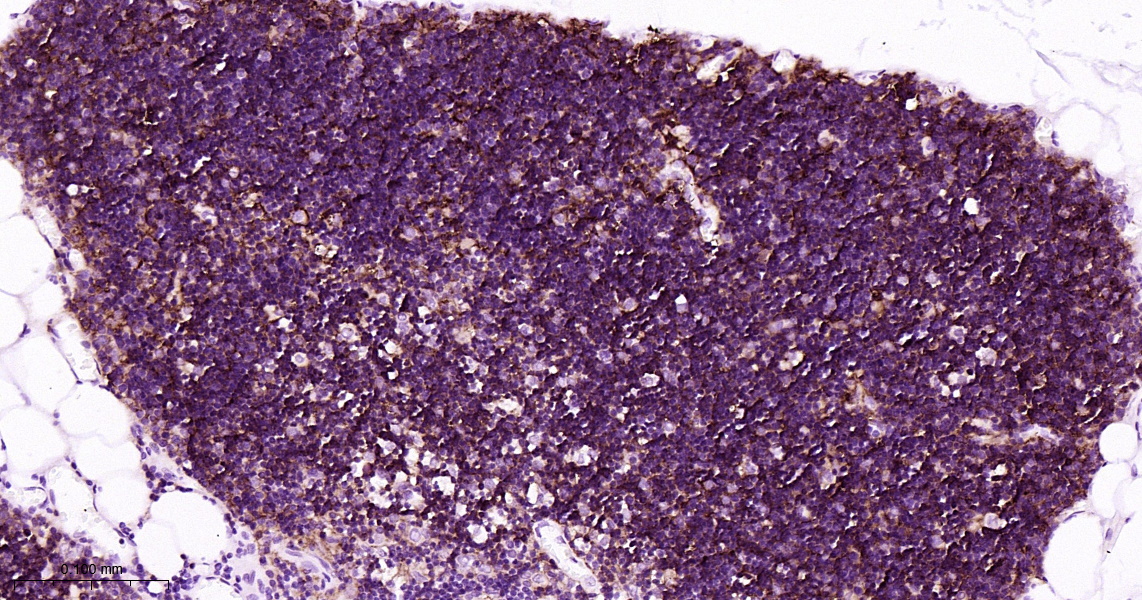

• IHC-P

IHC-P IHC-P1:100-500